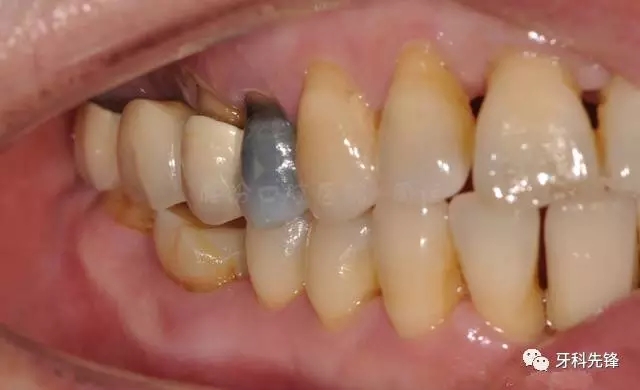

圖5拆除原修復體側位咬合照

640.webp (6).jpg

圖15臨時牙咬合照

640.webp (19).jpg